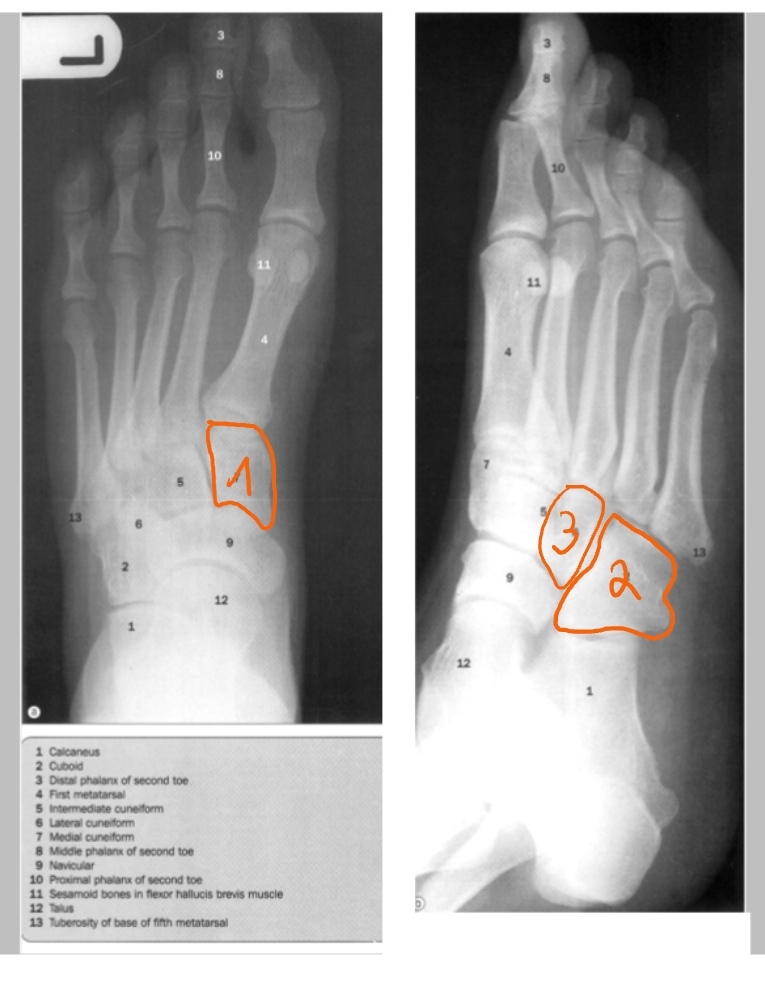

hallux

2 sesambeentjes

os cuneiforme mediale

os naviculare

os cuboideum

gewrichtslijn van Chopart

2 sesambeentjes

tuberositas van metatarsaal 5

os cuneiforme laterale

os cuboideum

os naviculare

talus

calcaneus

gewrichtslijn van Lisfranc

gewrichtslijn van Chopart